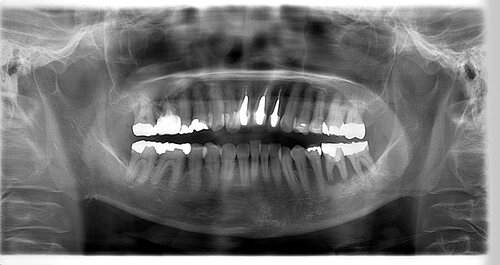

インプラント治療の症例2

レントゲン写真

- Befor

- After

| 年齢 | 50代・男性 |

|---|---|

| 主訴 | 左上7番 左下5番7番 |

| 治療内容 | ・インプラント埋入 ※1:GBR(骨造成)・・・骨再生誘導法。骨の高さや厚みを人工骨や人工膜などを使用し再生する方法 |

| 治療費 | 合計:1,809,500円(税込) ■内訳 ・左上7番 ・左下5番7番 |

| 治療期間 | 左上7番約1年 左下5番7番約10ヵ月 |

| 治療方針 | 左上7番は昔他院で被せものをしており、被せものの中が歯ぐきの中まで虫歯になっていたため抜歯せざるを得ない状態だった。抜歯と同時に骨造成を行い、骨が出来るまで4ヵ月待ってからインプラントを埋入した。 ※2ポンティック・・・歯のない部分を補うダミーの歯。 |

| 担当者所見 | 元々金属の被せものが多く入っていたため、2次カリエス※3が多かった。今回は金属ではなく、ジルコニアを使用し、2次カリエスにならないよう、患者様にはブラッシング指導とメンテナンスの重要性をお伝えした。 ※3二次カリエス・・・詰め物や被せものを入れた歯が虫歯になること。 |